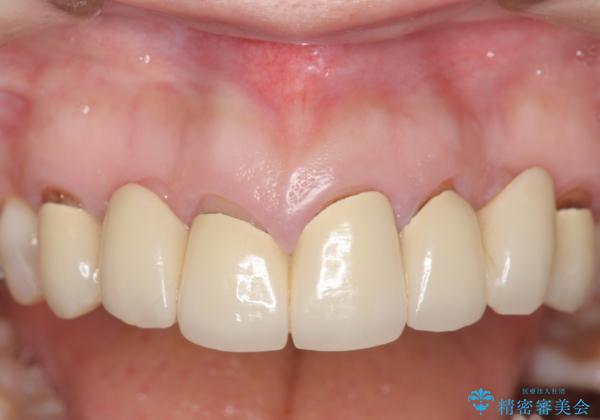

オールセラミッククラウン 前歯の被せ物を綺麗に

- 昔治療した前歯の被せ物の見た目を改善したいといらっしゃった方の症例です。

左上4番目の歯から右上3番目の歯まで計7歯のクラウンを除去し、オールセラミッククラウンによる補綴を行いました。

今回用いたオールセラミッククラウンはジルコニアフレームという白い素材の上にセラミックを盛っているため、審美性が非常に高いのが特徴です。